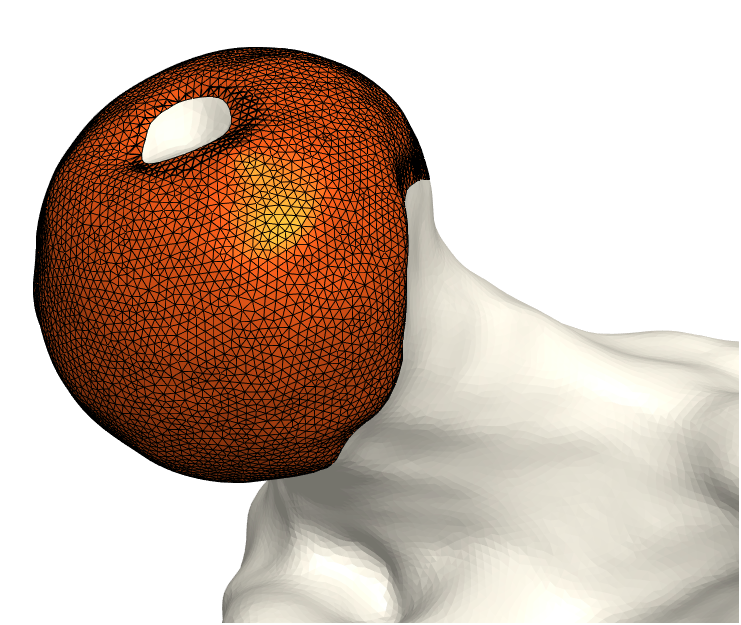

That is, we extrude each vertex 𝐯jsubscript𝐯𝑗\mathbf{v}_{j} in the direction of its normal by the displacement wjsubscript𝑤𝑗w_{j}. As a final step, we invert the bone-attached face normals before collecting the three disjoint sets of faces and vertices into a single mesh, (𝒱C,C)subscript𝒱𝐶subscript𝐶(\mathcal{V}_{C},\mathcal{F}_{C}). Observe in Fig. 3 the cartilage sub-surfaces combined into a single mesh.

Refer to caption

(a) Femoral cartilage.

(b) Femoral cartilage.

(c) Pelvic cartilage.

Figure 3: The final cartilage generated by our method for a femur (a), (b) and a pelvis (c). Notice how the cartilage aligns with the anatomical lines.